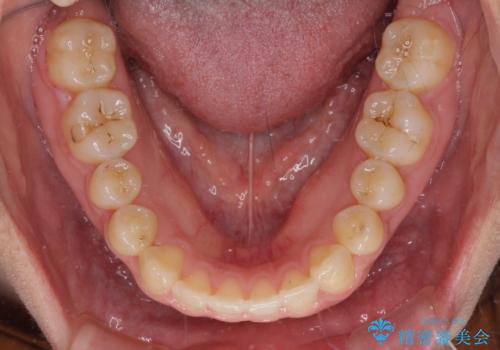

治療開始後すぐに妊娠され、つわりと闘いながらの矯正治療となりました。

上下顎でゴムかけを行ったのですが、早く終わらすためにしっかりと装着していただき、無事出産前に装置を外すことができました。